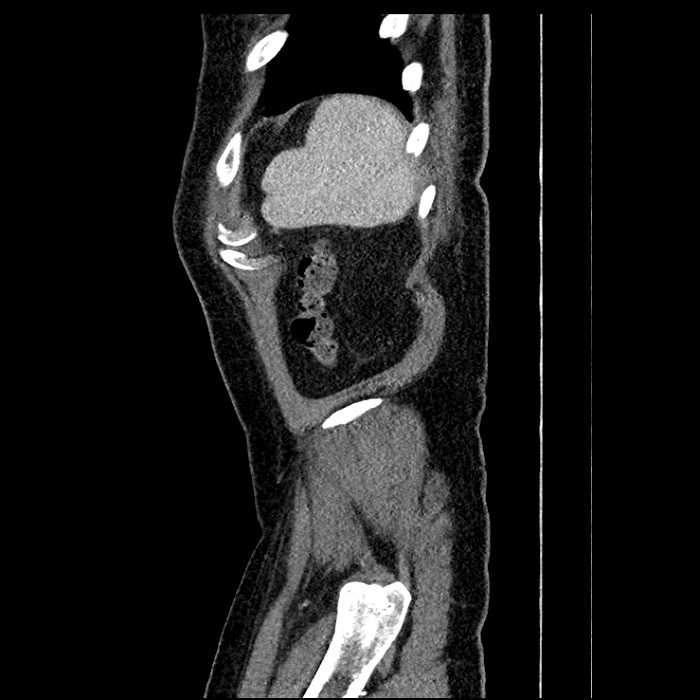

• Large fluid density structure in hepatic segments 7 and 8 measuring 10 x 7 x 7 cm with internal septation and circumferential ill-defined low density compatible with edema

• Hepatic abscess

Acute sigmoid diverticulitis complicated by a small contained perforation and a large abscess in the right hepatic lobe. Additional small subcapsular abscesses along the anterior margin of the left hepatic lobe.

• The classic CT imaging appearance is a double target sign with internal low density surrounded by an internal enhancing rim (capsule) and a low density external rim (edema)

• Abscesses may be unilocular or multilocular

• Gas is present in a minority of cases

Hepatic abscess showing the double target sign with low density internally surrounded by a thin inner enhancing rim (red arrow) and ill-defined outer low density rim (yellow arrow). Blue arrow indicates an internal septation. Red arrows: additional smaller subcapsular abscesses. Red arrow: focal contained perforation associated with diverticulitis.